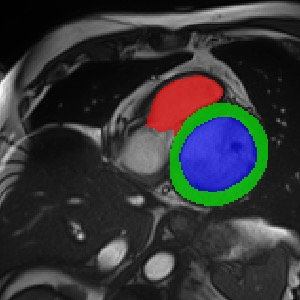

Transformers, the default model of choices in natural language processing, have drawn scant attention from the medical imaging community. Given the ability to exploit long-term dependencies, transformers are promising to help atypical convolutional neural networks (convnets) to overcome its inherent shortcomings of spatial inductive bias. However, most of recently proposed transformer-based segmentation approaches simply treated transformers as assisted modules to help encode global context into convolutional representations without investigating how to optimally combine self-attention (i.e., the core of transformers) with convolution. To address this issue, in this paper, we introduce nnFormer (i.e., Not-aNother transFormer), a powerful segmentation model with an interleaved architecture based on empirical combination of self-attention and convolution. In practice, nnFormer learns volumetric representations from 3D local volumes. Compared to the naive voxel-level self-attention implementation, such volume-based operations help to reduce the computational complexity by approximate 98% and 99.5% on Synapse and ACDC datasets, respectively. In comparison to prior-art network configurations, nnFormer achieves tremendous improvements over previous transformer-based methods on two commonly used datasets Synapse and ACDC. For instance, nnFormer outperforms Swin-UNet by over 7 percents on Synapse. Even when compared to nnUNet, currently the best performing fully-convolutional medical segmentation network, nnFormer still provides slightly better performance on Synapse and ACDC.